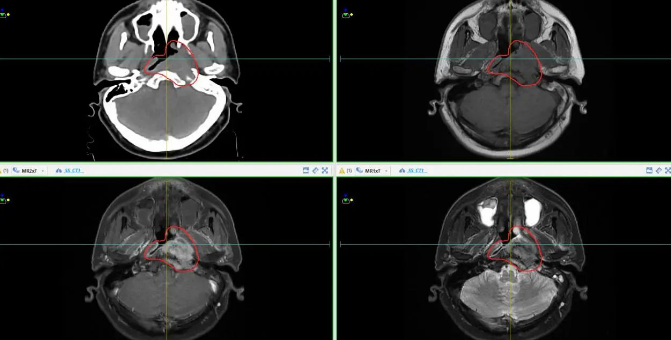

常态化磁共振模拟定位(实现放疗靶区雕刻式精准勾画)